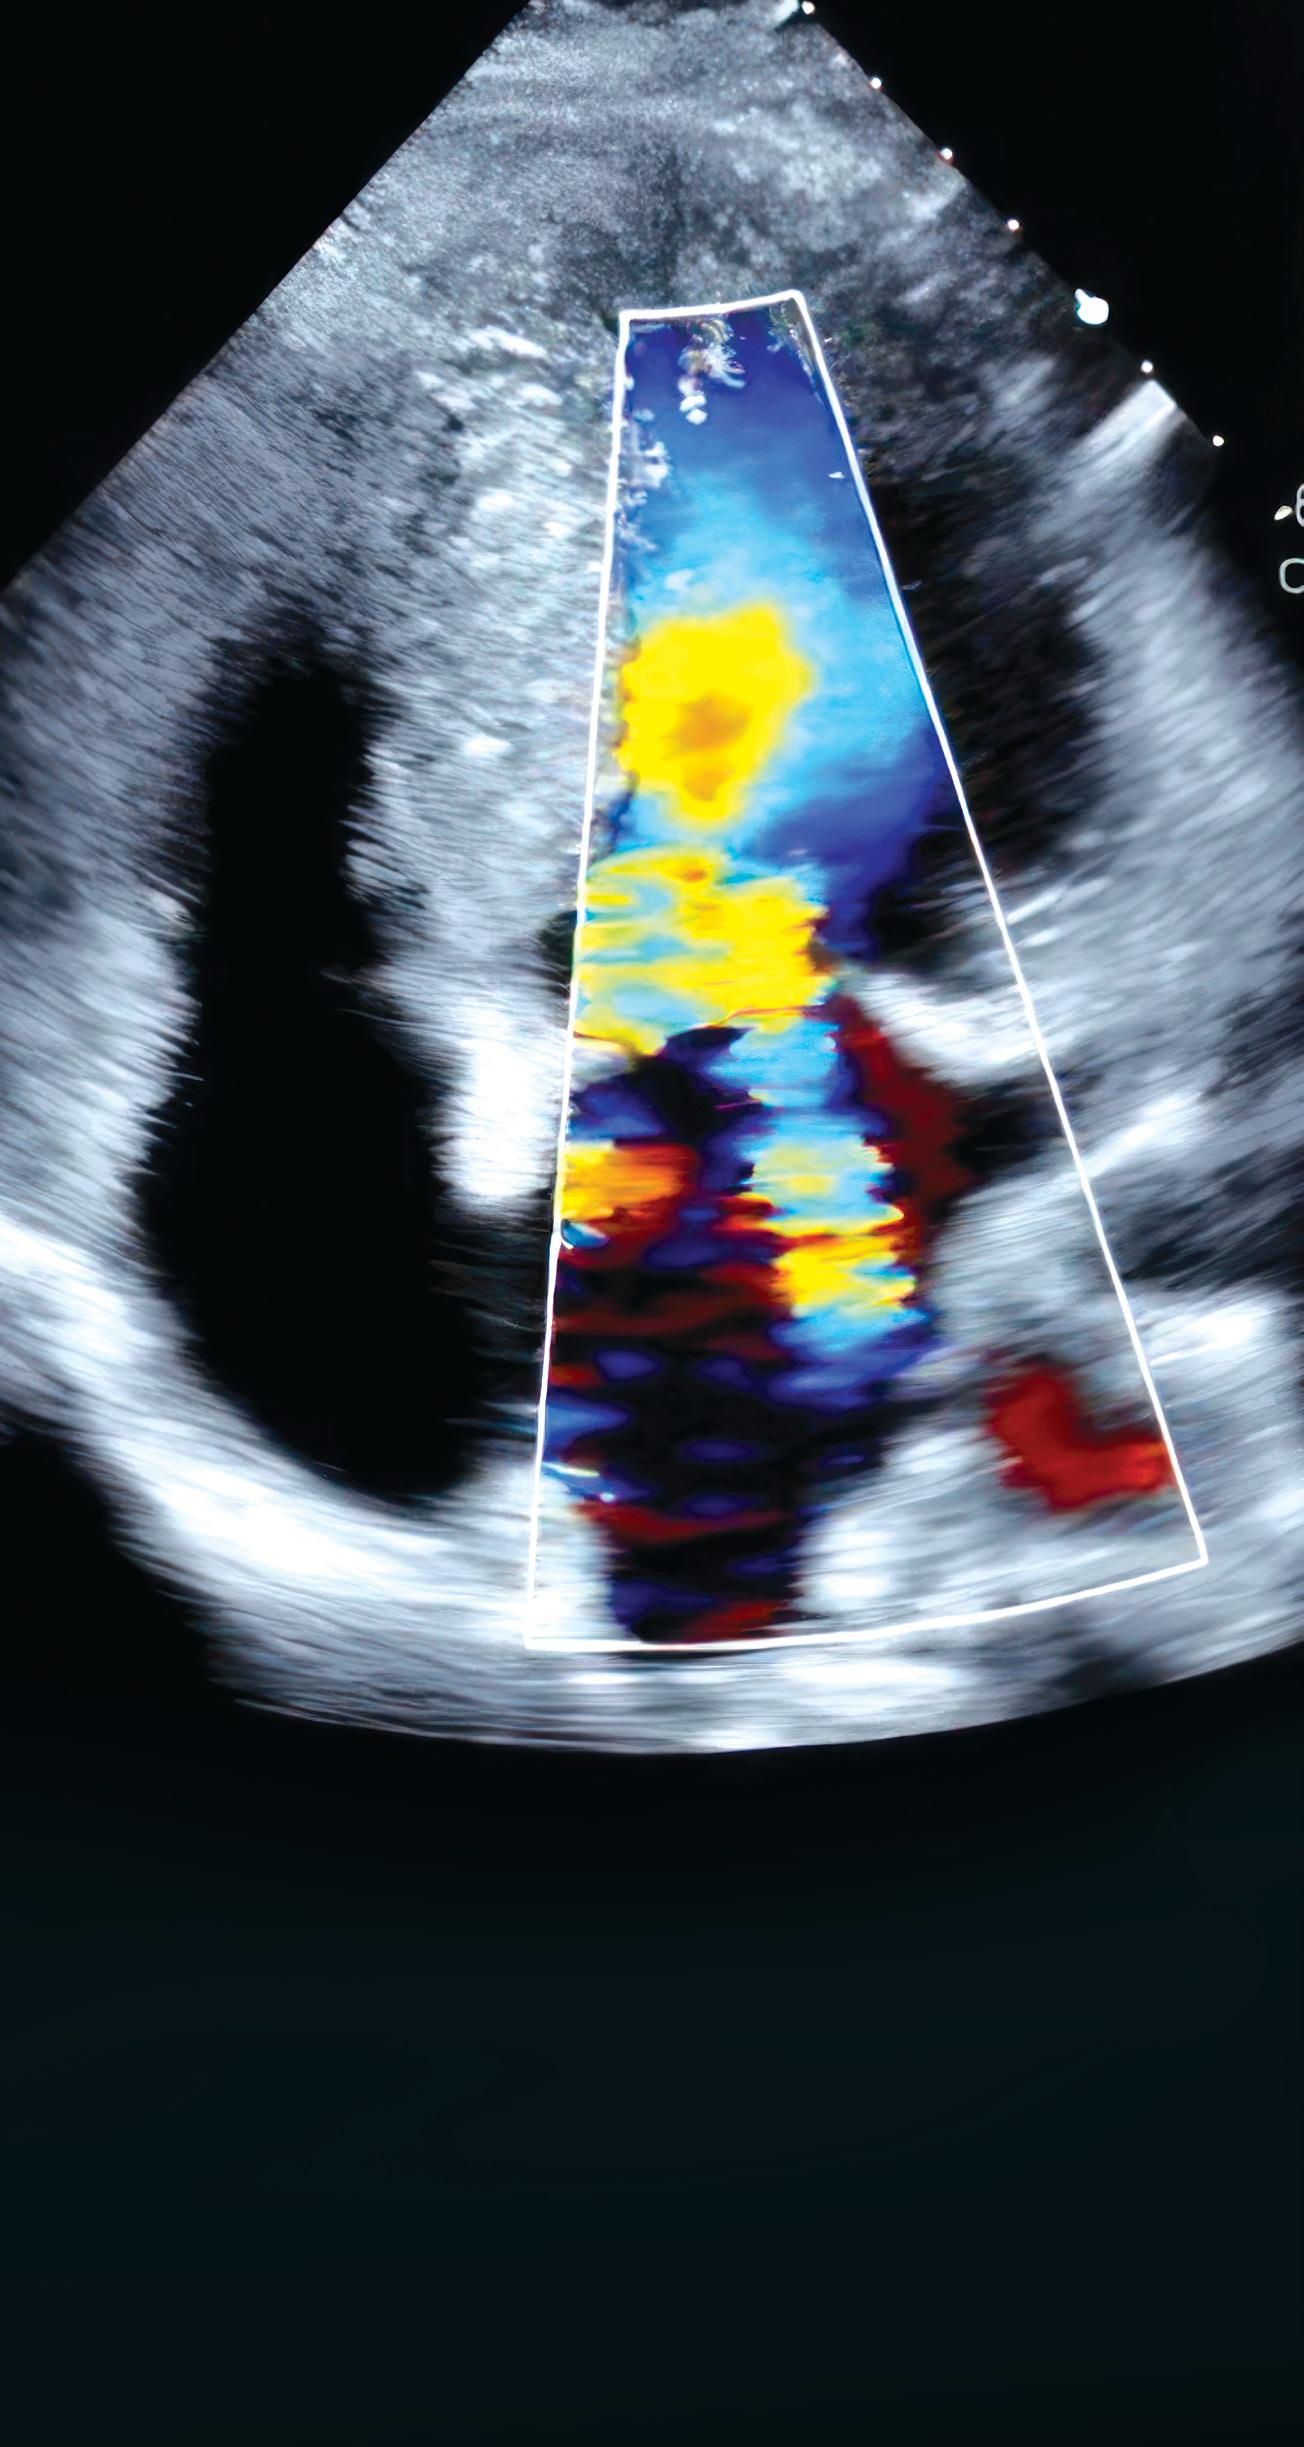

Transthoracic echocardiography showing systolic anterior motion of the mitral valve due to HCM.

Transthoracic echocardiography (TTE) is the first-line diagnostic test in the evaluation of HCM. TTE is not specific for the diagnosis of HCM but it helps exclude other structural abnormalities that cause increased LV wall thickness, including a subaortic membrane and aortic valve stenosis. TTE findings typical of HCM include increased LV wall thickness, systolic anterior motion of the mitral valve, LV outflow tract obstruction (LVOTO), abnormal diastolic function and abnormal myocardial deformation or strain. CMR is usually performed following an abnormal TTE indicative of HCM.